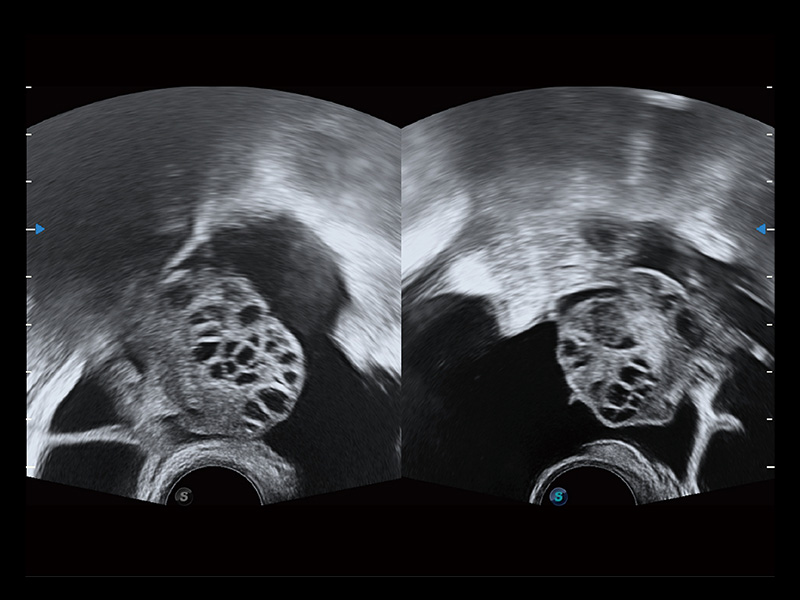

“生育问题”即关系民族复兴,也关系亿万家庭的幸福。随着婚育年龄推迟、社会压力增加等因素,越来越多人群也面临着“生不出、生不好”的问题。辅助生殖作为治疗不孕不育最有效的方法之一,也逐渐成为育儿新希望。而超声检查能为生殖需求人群的初诊评估提供宝贵的信息。 P20 Elite是db真人体育官网匠心打造的一款生殖应用型彩超。她继承db真人体育官网高端极光平台,突破性地将多款新型芯片及硬件模块进行整合,均衡了高端系统性能与小巧灵动机身。P20 Elite卓越的图像质量搭载专科探头,旨在为您提供全面的辅助生殖解决方案。

P20 Elite配备了丰富的生殖探头群和临床应用功能,在卵泡监测、穿刺取卵、胚胎移植、妊娠确认等领域,为生殖需求人群提供了新的临床机会,重新定义高端超声如何应用于生殖健康检查。

P20 Elite可选配23.8英寸高分辨率显示器,提供出色的对比分辨率,图像清晰更清晰,方便医生诊断观察。